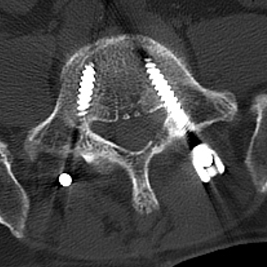

▲术前MRI

然而患者需行多节段腰椎融合

入院后,陈勇主任在科室组织了病例讨论并表示:常规保守治疗只能缓解症状无法从根本上解决病根。目前,患者已保守治疗1月,症状未见明显缓解,且进行性加重。影像学可见腰椎间盘突出伴椎管狭窄严重程度高,有明确的手术指征,结合患者及其家属的意愿,选择腰椎后路减压植骨融合内固定术。

▲3D打印直观显示椎体结构,指导手术精准置钉